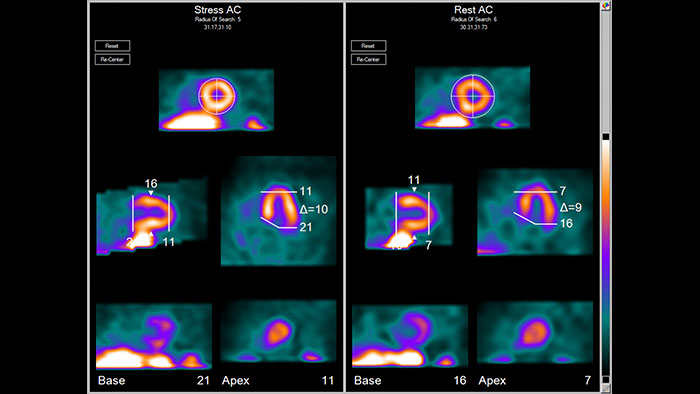

Astonish Reconstruction

NM Astonish Reconstruction

L’algorithme avancé de reconstruction NM Astonish Reconstruction utilise la technique de double filtrage de Philips pour réduire le bruit et améliorer la résolution et l’homogénéité de l’image reconstruite. Il est par ailleurs possible d’associer une carte d’atténuation TDM à NM Astonish Reconstruction pour bénéficier d’une fonction de correction par atténuation. L’amélioration du rapport signal/bruit assure une qualité d’image équivalente tout en réduisant la durée d’acquisition SPECT, ce qui accroît la productivité, améliore le confort du patient et limite les artefacts de mouvement.

Avantages

• Offre plusieurs avantages cliniques, y compris une meilleure résolution d’image et une meilleure efficacité des processus de travail.

• Permet l’imagerie TI-201, In-111, Ga-67, I-123 ou I-131 et la gammatomographie cardiaque avec un temps d’acquisition réduit de moitié en utilisant les systèmes Philips pris en charge pour améliorer l’efficacité des processus de travail tout en conservant la qualité d’image.

• Augmente la fiabilité des interprétations et la précision des diagnostics.

• Applicable à des études SPECT avec Tc-99m pour la plupart des procédures d’imagerie moléculaire.

• Compatible uniquement avec les caméras Philips suivantes : CardioMD (logiciel d’acquisition version 2.x), Forte, BrightView, BrightView X, BrightView XCT, SkyLight et Precedence.